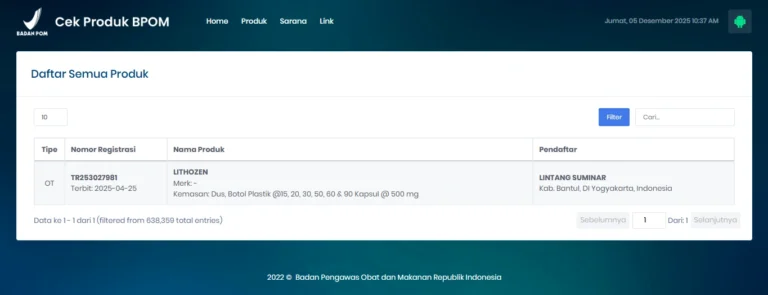

Terdaftar BPOM